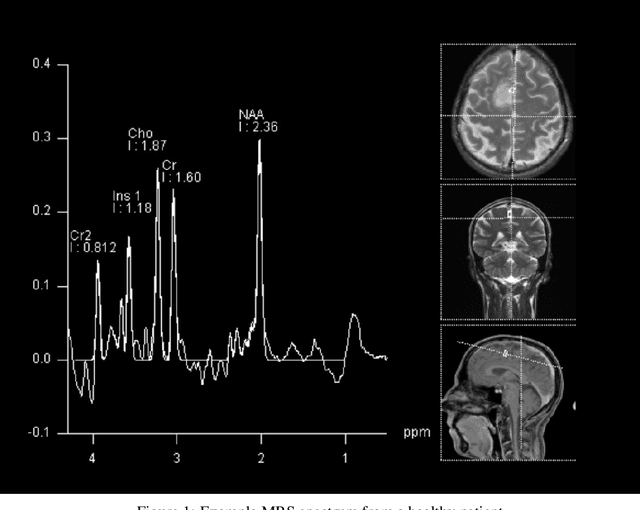

Abstract:We apply deep learning (DL) on Magnetic resonance spectroscopy (MRS) data for the task of brain tumor detection. Medical applications often suffer from data scarcity and corruption by noise. Both of these problems are prominent in our data set. Furthermore, a varying number of spectra are available for the different patients. We address these issues by considering the task as a multiple instance learning (MIL) problem. Specifically, we aggregate multiple spectra from the same patient into a "bag" for classification and apply data augmentation techniques. To achieve the permutation invariance during the process of bagging, we proposed two approaches: (1) to apply min-, max-, and average-pooling on the features of all samples in one bag and (2) to apply an attention mechanism. We tested these two approaches on multiple neural network architectures. We demonstrate that classification performance is significantly improved when training on multiple instances rather than single spectra. We propose a simple oversampling data augmentation method and show that it could further improve the performance. Finally, we demonstrate that our proposed model outperforms manual classification by neuroradiologists according to most performance metrics.

Abstract:The application of Deep Learning (DL) for medical diagnosis is often hampered by two problems. First, the amount of training data may be scarce, as it is limited by the number of patients who have acquired the condition to be diagnosed. Second, the training data may be corrupted by various types of noise. Here, we study the problem of brain tumor detection from magnetic resonance spectroscopy (MRS) data, where both types of problems are prominent. To overcome these challenges, we propose a new method for training a deep neural network that distills particularly representative training examples and augments the training data by mixing these samples from one class with those from the same and other classes to create additional training samples. We demonstrate that this technique substantially improves performance, allowing our method to reach human-expert-level accuracy with just a few thousand training examples. Interestingly, the network learns to rely on features of the data that are usually ignored by human experts, suggesting new directions for future research.